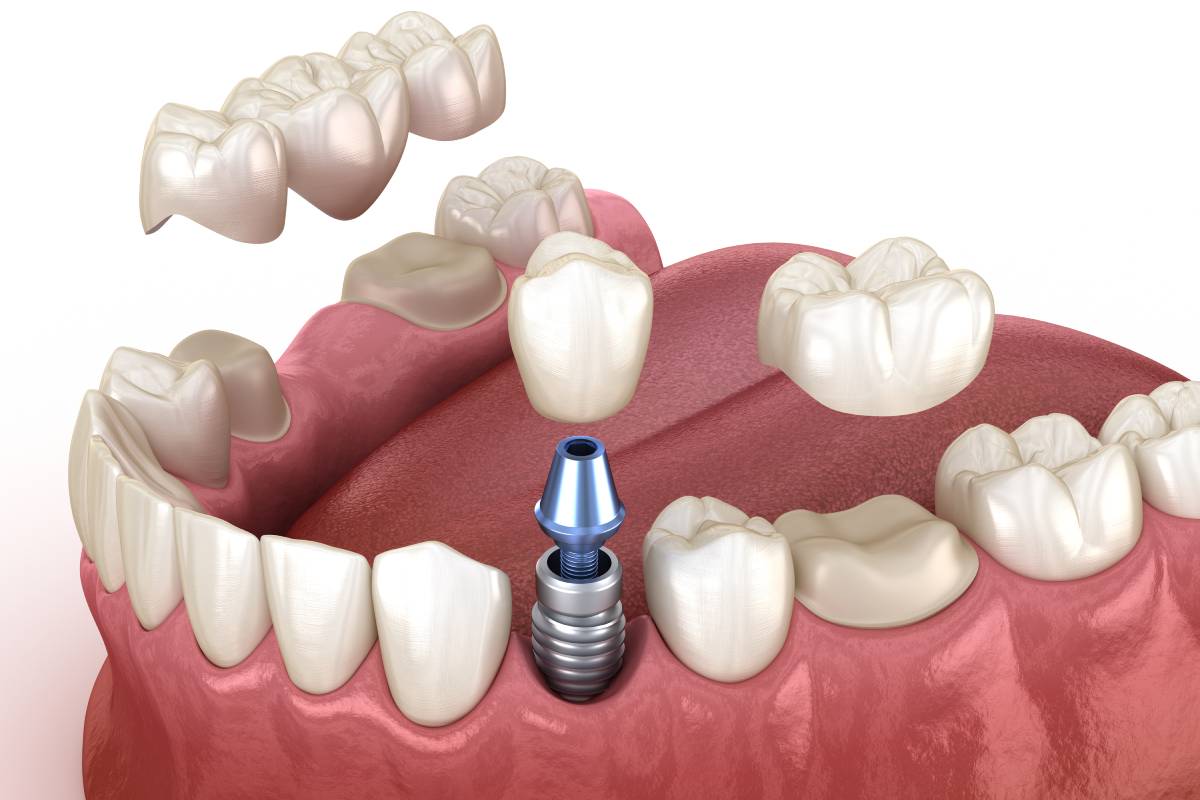

What Are Dental Crowns and Bridges?

A dental crown is a protective cap placed over a damaged or weakened tooth to restore its strength, shape, and appearance. A dental bridge is used to replace one or more missing teeth by anchoring artificial teeth to nearby natural teeth.

Both options are designed to look natural and blend seamlessly with your smile. The Colgate Oral Care resource highlights that crowns and bridges help restore chewing ability while protecting remaining teeth from shifting.